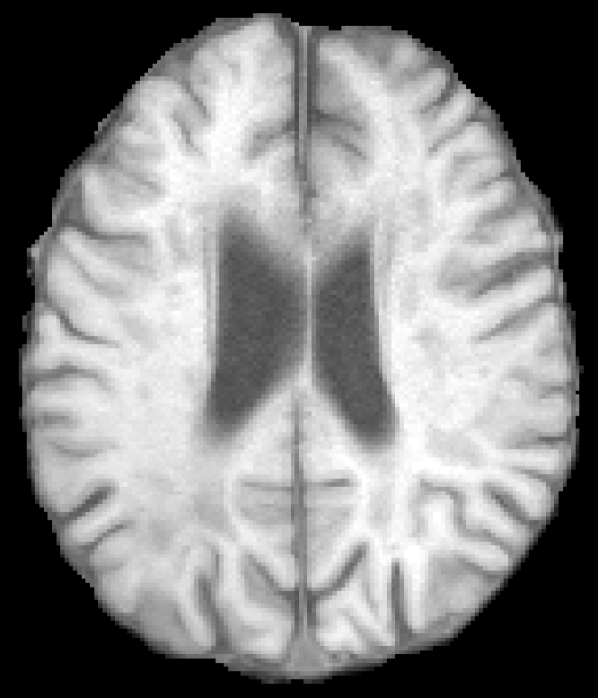

The given images are first pre-processed with a symmetric modality augmentation to allow learning of features based on the symmetry of brain hemispheres despite the small receptive field of the used patches. Explicit symmetry information was already shown to improve results for chronic stroke lesion segmentation [19]. In our case, instead of using one patch per hemisphere in a multi-path network we use a single joint patch with a single-path network. In practice, we augment the provided modality images with symmetric versions that swap the left and right hemispheres. We first flip one of the images along the mid-sagittal axis and then we apply FSL FLIRT [20] to perform a linear registration between the original and flipped image. Finally, the rest of modalities are registered using the same transformation. Figure 1 shows an example of the resulting symmetrically augmented modalities. These are then appended to the provided ones, effectively doubling the number of images for each patient. In this way, a single extracted patch will also include intensity information from the opposite hemisphere.

Refer to caption

(a) T1

(b) T2

(c) DWI

(d) FLAIR

Figure 1: Provided and symmetrically augmented modalities from case 2 of the SISS training images.